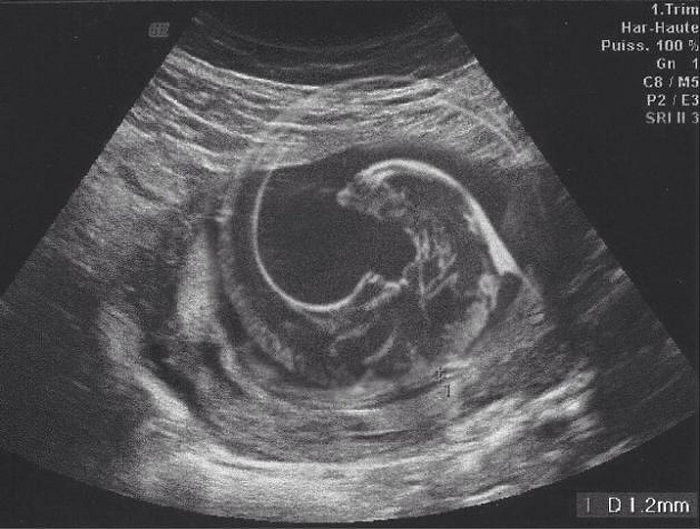

3. A gyermekünkről készült ultrahang képet az én e-mail címemre küldték át a vizsgálat után. Mielőtt átküldtem volna a feleségemnek, poénból rászerkesztettem egy alient a képre. A feleségemnek nem tűnt fel, hogy valami nem stimmel a képpel, ezért tovább küldte az összes rokonunknak.